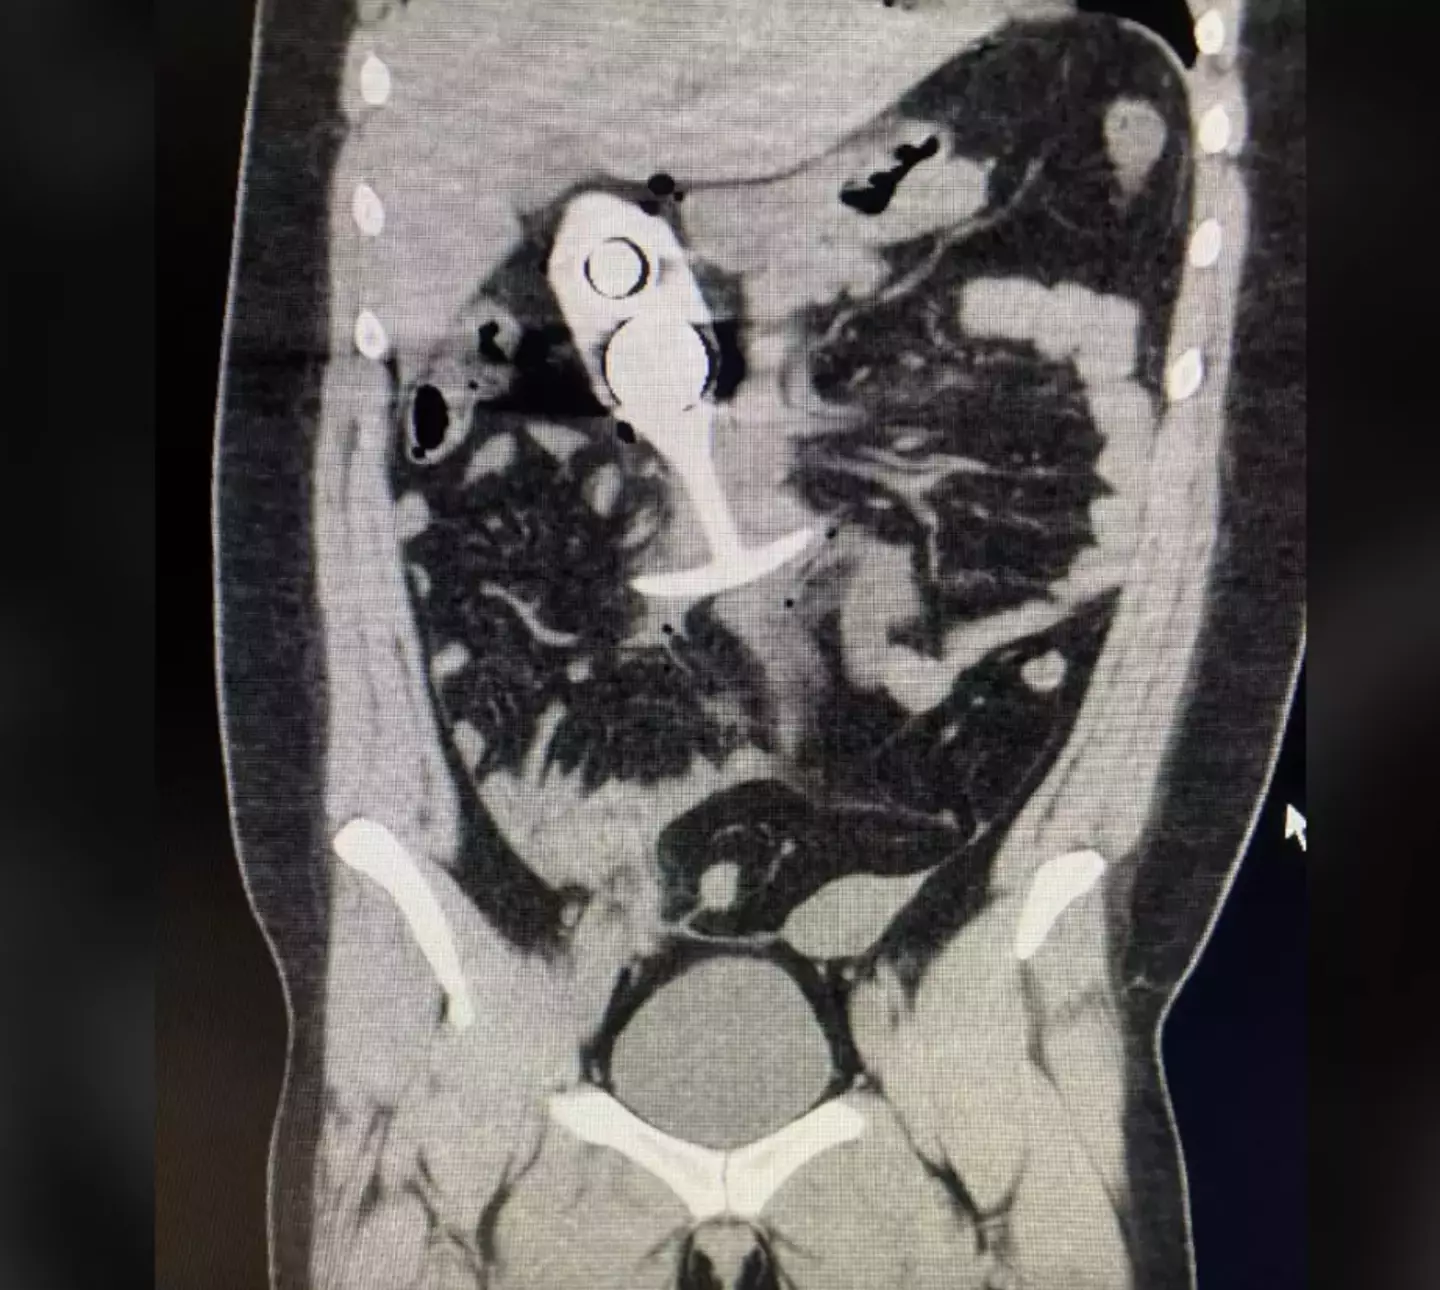

An image was shared on Reddit of the woman’s alleged scan, but it has not been confirmed that this picture is in relation to this particular incident.

A scan showing someone with a butt plug inside them (Reddit)